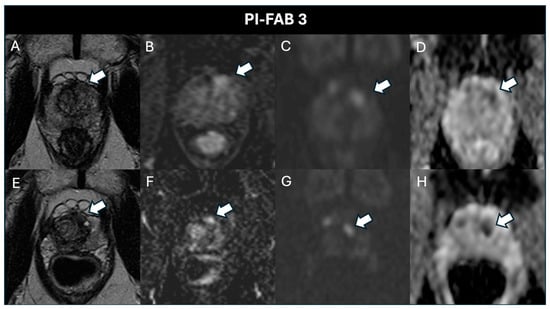

| PI-FAB 3, n (%) | 3 (4.4) | 0 (0) | 0 (0) |